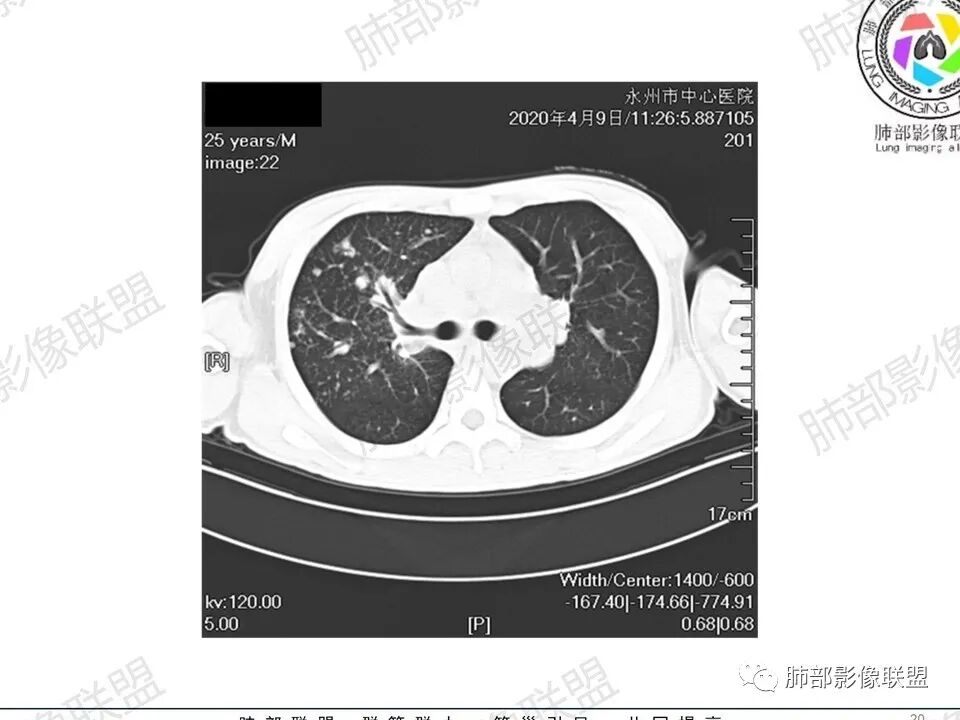

那个人:青年男性,慢性病程,咳嗽气促,伴盗汗胸痛。实验室,贫血,血沉快,C反应蛋白升高,低蛋白血症。影像,双肺散在斑片影,结节影,伴树芽,斑片影源支气管血管束分布,支气管走形自然,结节影有小空洞,有些周围有磨玻璃成分,小结节有些成串珠样改变,纵隔肺门淋巴结肿大,心腔低密度。考虑淋巴增值类疾病,结核?淋巴瘤?结节病?鉴别血管炎,实验室,影像不太支持

穿越七海的风:双肺多发结节斑片影,支气管通畅,间质浸润,纵隔肺门肿大淋巴结,考虑淋巴瘤?白血病浸润?结节病?

薏米:青年男性,慢性咳嗽,咳痰,气短,贫血,淋巴细胞低,尿隐血阴性,双肺散在多发结节,斑片,树芽影,支气管充气,肺门,纵隔淋巴结肿大,融合趋势,考虑淋巴瘤,鉴别结核

甄德强:年轻男性,慢性起病,双肺多发斑片影,结节影及粟粒点状影,纵隔及双肺门淋巴结肿大,似乎密度不均,结核中度症状,血沉快,一元论考虑结核,鉴别诊断结节病。

一切∮随缘:双肺多发大小不等结节,结节密度高,边缘清楚,部分结节内可见血管穿行,另右肺长条状实变影,内部可见支气管充气征,局部支气管壁增厚,双肺多发小树丫,双肺门及纵隔淋巴结肿大,部分融合,无增强,对淋巴结坏死无法判断,临床:年轻男性慢性病史急性加重,血象、CRP、ESR高,考虑一元论:结核(年龄加影像都符合),二元论:结节病或淋巴瘤+结核(建议CT增强及淋巴结穿刺),无原发肿瘤病史,癌性淋巴管炎代排。

刘L:纵隔多发淋巴结肿大,自肺门向上呈对称性分布,部分融合,内密度均匀;双肺散在分布大小不等结节,边界清晰,右肺中叶部分伴有实变,首先考虑结节病,建议增强扫描排除肺结核。

男性,25岁,咳嗽咳痰1年,气促两月,加重一天,伴盗汗胸痛。CT示双肺散在斑片影,结节影,树芽征,部分周围伴磨玻璃影,以右肺上叶明显,纵隔及双肺门可见多发淋巴结肿大,部分融合,青年人,病史较长,首先考虑结核,不排除结核合并结节病可能。

3、影像表现:双肺散在斑片影及结节影,部分结节内可见血管穿行,斑片影沿支气管血管束分布,近胸膜侧病变收缩不明显。部分中央淋巴间质增厚,小叶间隔增厚。病灶内支气管穿行,部分支气管略扩张。局部小结节呈串珠样改变。纵隔、肺门区、锁骨上及腋窝淋淋巴结肿大,部分有融合。心腔低密度。脾大。

2.双肺多发片影及结节影,边界可分辨,右肺中上叶较为密集,没有胸膜下分布优势。病灶实性密度为主,未见钙化及液化。

3.右肺较多微小结节,密度较为浅淡,部分沿血管束分布,未见沿小叶间隔及叶间裂分布结节影,未见典型的终末气道树芽。

4.病灶区域穿行支气管显示良好,未见壁增厚及管腔狭窄。

5.双肺门及纵隔淋巴结显著增大,这改变相当显眼。这里强调“双肺门”及“多发”!